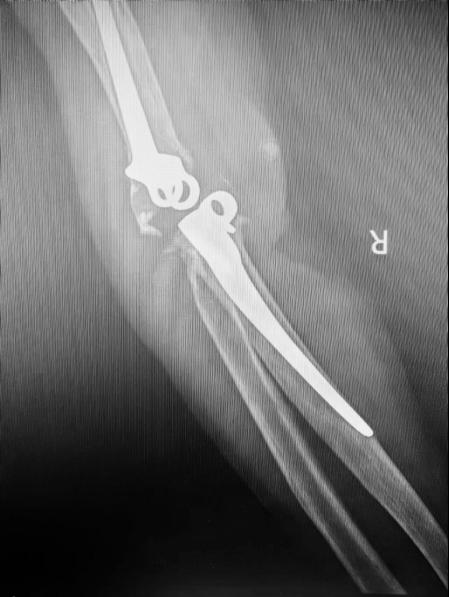

患者是一名55岁的中年男性,23年前因严重车祸伤于我院由王坤正教授完成右肘关节置换术,术后恢复良好。1年前患者再次出现右侧肘关节疼痛,外院肘关节X片提示假体转轴磨损脱落合并脱位。患者第一时间联系了我科,要求行翻修手术。入院时右侧肘关节无活动度,功能基本丧失,患者的工作和生活受到了极大的影响,深感痛苦。

与其他人工关节置换术相比,全肘关节置换术在设计和手术技术上要求更高。肘关节的复杂运动特性使得术后假体活动和稳定性的控制成为一大挑战。此外,假体在各种体位和活动中的松动、断裂和磨损风险,对手术医师的操作准确性与熟练度提出了严格要求。该患者术前肘关节假体肱骨侧及尺骨侧均几乎穿出骨皮质,髓腔形态异常,为确保手术成功,关节与足踝病区团队完善术前讨论,为该患者设计了个性化的3D打印肘关节假体,并提前模拟了手术假体安装过程。在王坤正教授的指导下,杨佩教授、王春生副主任医师经过精细操作,最终使这一例复杂肘关节置换术最终成功实施,使患者可以更快地恢复肘关节功能,进行正常的日常生活活动,提高生活质量。